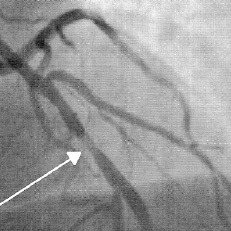

Herr Peter willigt in eine Herzkatheteruntersuchung ein. Hierbei wird der Blutfluss in den Koronararterien dargestellt, Einengungen der Koronararterien (Stenosen) oder Gefässverschlüsse werden sichtbar gemacht, Abb. 1. Es bestätigt sich der Verdacht: Die linke Koronararterie ist an einer Stelle fast verschlossen. Der Herzspezialist erklärt den Befund am Bildschirm. Es ist gut vorstellbar, dass der Herzmuskel in diesem Bereich bei Anstrengungen vermindert durchblutet wird.

Abb. 1

90%ige Stenose